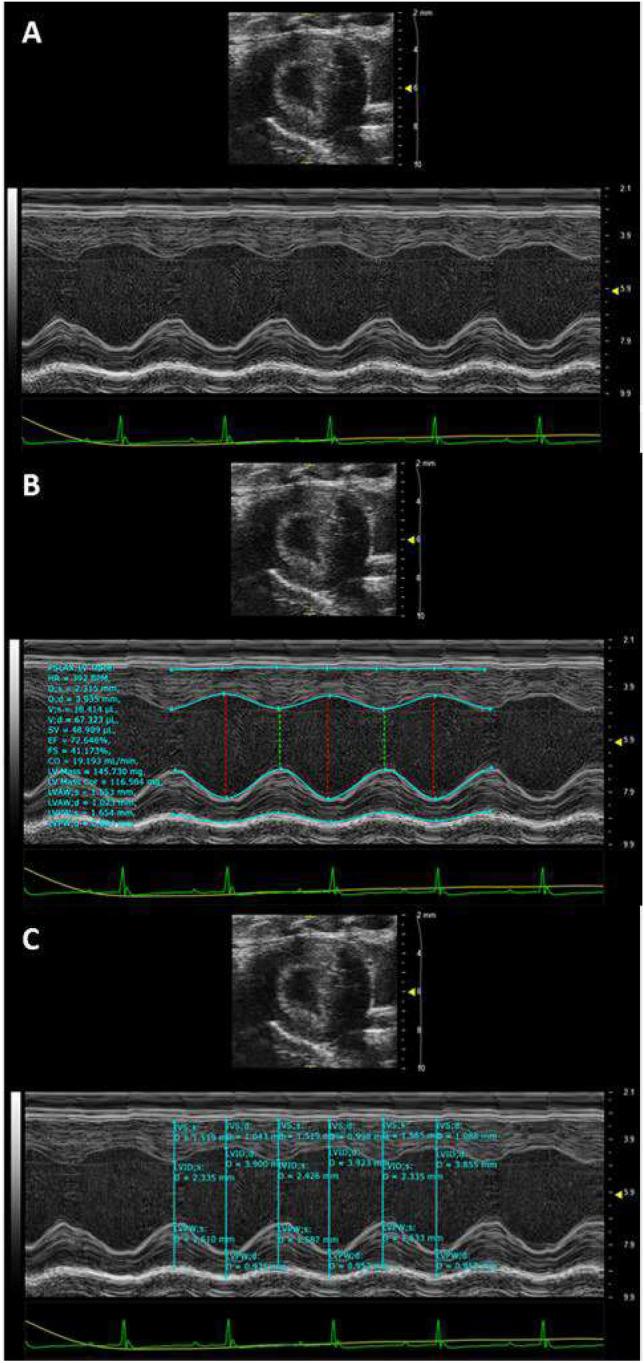

In individuals with Marfan Syndrome (MFS), fibrillin-1 gene (FBN1) mutations can lead to vascular wall weakening and dysfunction. The experimental mouse model of MFS (Fbn1) has been advantageous in investigating MFS-associated life-threatening aortic aneurysms. It is well established that the MFS mouse model exhibits an accelerated-aging phenotype in elastic organs like the aorta, lung, and skin. However, the impact of Fbn1 mutations on the in vivo function and structure of various artery types with the consideration of sex and age, has not been adequately explored in real-time and a clinically relevant context. In this study, we investigate if Fbn1 mutation contributes to sex-dependent alterations in central and cerebral vascular function similar to phenotypic changes associated with normal aging in healthy control mice. In vivo ultrasound imaging of central and cerebral vasculature was performed in 6-month-old male and female MFS and C57BL/6 mice and sex-matched 12-month-old (middle-aged) healthy control mice. Our findings confirm aortic enlargement (aneurysm) and wall stiffness in MFS mice, but with exacerbation in male diameters. Coronary artery blood flow velocity (BFV) in diastole was not different but left pulmonary artery BFV was decreased in MFS and 12-month-old control mice regardless of sex. At 6 months of age, MFS male mice show decreased posterior cerebral artery BFV as compared to age-matched control males, with no difference observed between female cohorts. Reduced mitral valve early-filling velocities were indicated in MFS mice regardless of sex. Male MFS mice also demonstrated left ventricular hypertrophy. Overall, these results underscore the significance of biological sex in vascular function and structure in MFS mice, while highlighting a trend of pre-mature vascular aging phenotype in MFS mice that is comparable to phenotypes observed in older healthy controls. Furthermore, this research is a vital step in understanding MFS's broader implications and sets the stage for more in-depth future analyses, while providing data-driven preclinical justification for re-evaluating diagnostic approaches and therapeutic efficacy.

在马凡综合征(MFS)患者中,原纤维蛋白 1 基因(FBN1)突变可导致血管壁弱化和功能障碍。MFS 的实验小鼠模型(Fbn1)在研究与马凡综合征相关的危及生命的主动脉瘤方面具有优势。众所周知,MFS 小鼠模型的主动脉、肺和皮肤等弹性器官表现出加速衰老表型。然而,Fbn1 突变对不同类型动脉的体内功能和结构的影响,在实时和临床相关的背景下,尚未得到充分探讨。在这项研究中,我们研究了 Fbn1 突变是否导致中央和脑血管功能的性别依赖性改变,类似于与健康对照小鼠正常衰老相关的表型变化。对 6 月龄雄性和雌性 MFS 及 C57BL/6 小鼠以及年龄匹配的 12 月龄(中年)健康对照小鼠的中央和脑血管进行了体内超声成像。我们的研究结果证实了 MFS 小鼠的主动脉扩张(动脉瘤)和壁僵硬,但在雄性中更为严重。舒张期冠状动脉血流速度(BFV)没有差异,但 MFS 和 12 月龄对照小鼠的左肺动脉 BFV 下降,无论性别如何。在 6 月龄时,与年龄匹配的雄性对照组相比,MFS 雄性小鼠的大脑后动脉 BFV 降低,但雌性组之间没有差异。MFS 小鼠无论性别如何,二尖瓣早期充盈速度均降低。MFS 小鼠还表现出左心室肥厚。总之,这些结果强调了生物学性别在 MFS 小鼠血管功能和结构中的重要性,同时突出了 MFS 小鼠中血管提前衰老表型的趋势,与老年健康对照者观察到的表型相似。此外,这项研究是理解马凡综合征更广泛影响的重要一步,为更深入的未来分析奠定了基础,并为重新评估诊断方法和治疗效果提供了基于数据的临床前依据。